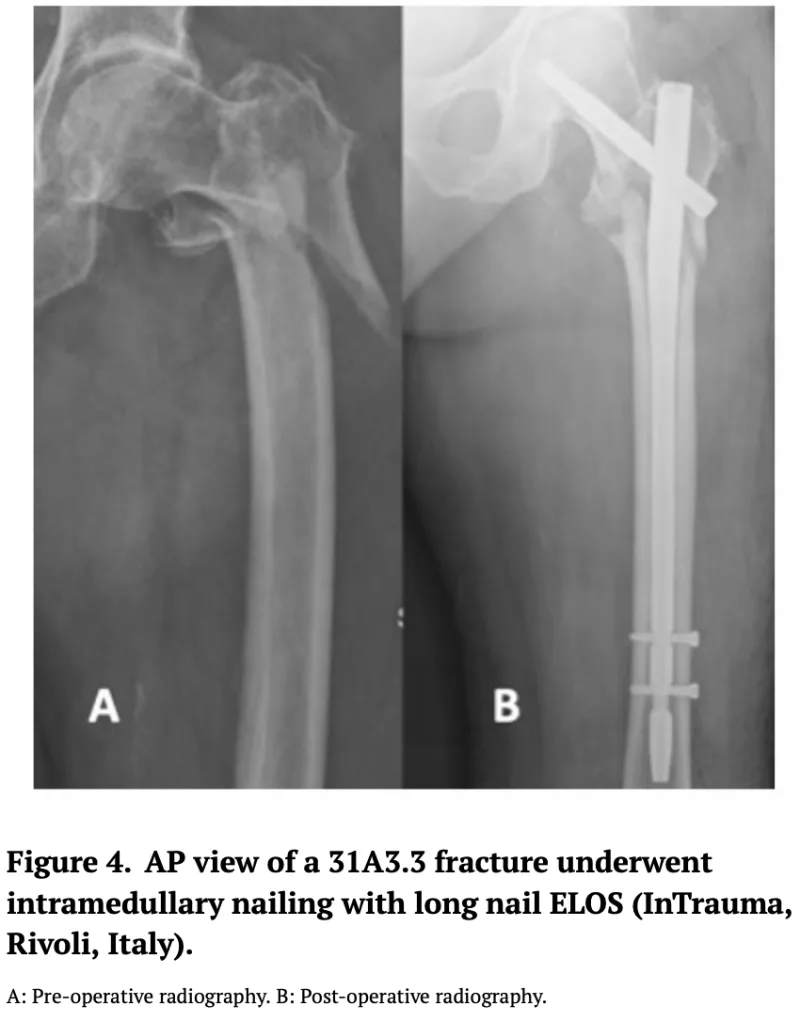

AO/OTA分類では, 31A3.3の逆斜骨折で, 不安定性が強いタイプでした.

大腿骨転子部骨折AO/OTA分類31A3.3の逆斜骨折に対する髄内釘固定術前後のX線像.

引用元:Marsillo E. Cephalomedullary nailing for reverse oblique intertrochanteric fractures 31A3 (AO/OTA). Orthop Rev (Pavia). 2022. 14.

骨折部を展開して, 外側に跳ね上がってズレていた骨を元の位置に戻してから, 髄内釘を挿入.